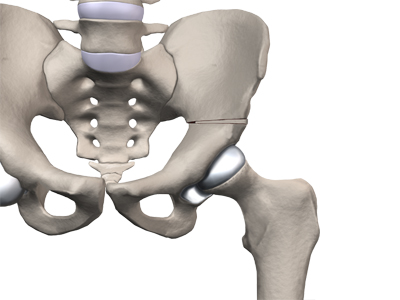

The hip joint is where the thighbone (femur) connects to the pelvis. The joint is made up of two parts. The upper end of the femur is shaped like a ball. It is called the femoral head. The femoral head fits into a socket in the pelvis called the acetabulum. This ball and socket joint is what allows us to move our leg in many directions in relation to our body.

In the growing child, there are special structures at the end of most bones called growth plates. The growth plate is sandwiched between two special areas of the bone called the epiphysis and the metaphysis. The growth plate is made of a special type of cartilage that builds bone on top of the end of the metaphysis and lengthens the bone as we grow. In the hip joint, the femoral head is one of the epiphyses of the femur.

The capital femoral epiphysis is somewhat unique. It is one of the few epiphyses in the body that is inside the joint capsule. (The joint capsule is the tissue that surrounds the joint.) The blood vessels that go to the epiphysis run along the side of the femoral neck and are in danger of being torn or pinched off if something happens to the growth plate. This can result in a loss of the blood supply to the epiphysis.